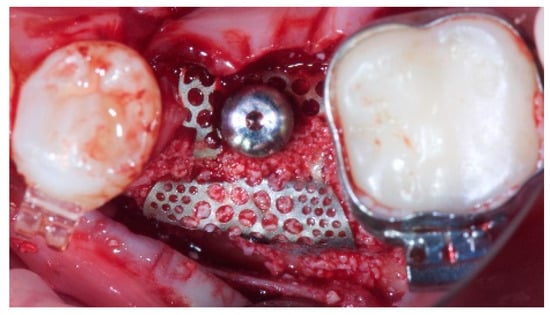

- Horizontal bone augmentation was evaluated at the CBCT scans, 1 mm below the original bone crest. The volumetric data were superimposed using the adjacent teeth as reference points, and a new generated set of DICOM data was stored as a separately files. Measures were taken before and after the treatment, and the difference of these two measurements was taken as horizontal bone augmentation (Figure 9).

- Volumetric measurements of the reconstructed bone was performed automatically on the merged CBCT set of volumetric data, using the Fusion module of the OnDemand 3D software (Cybermed Inc., Seoul, Korea), according a previously published protocol [8].

| Mean horizontal alveolar ridge (mm) | 2.92 ± 0.48 (95% CI 2.68–3.16) | 8.29 ± 2.14 (95% CI 7.59–8.99) |